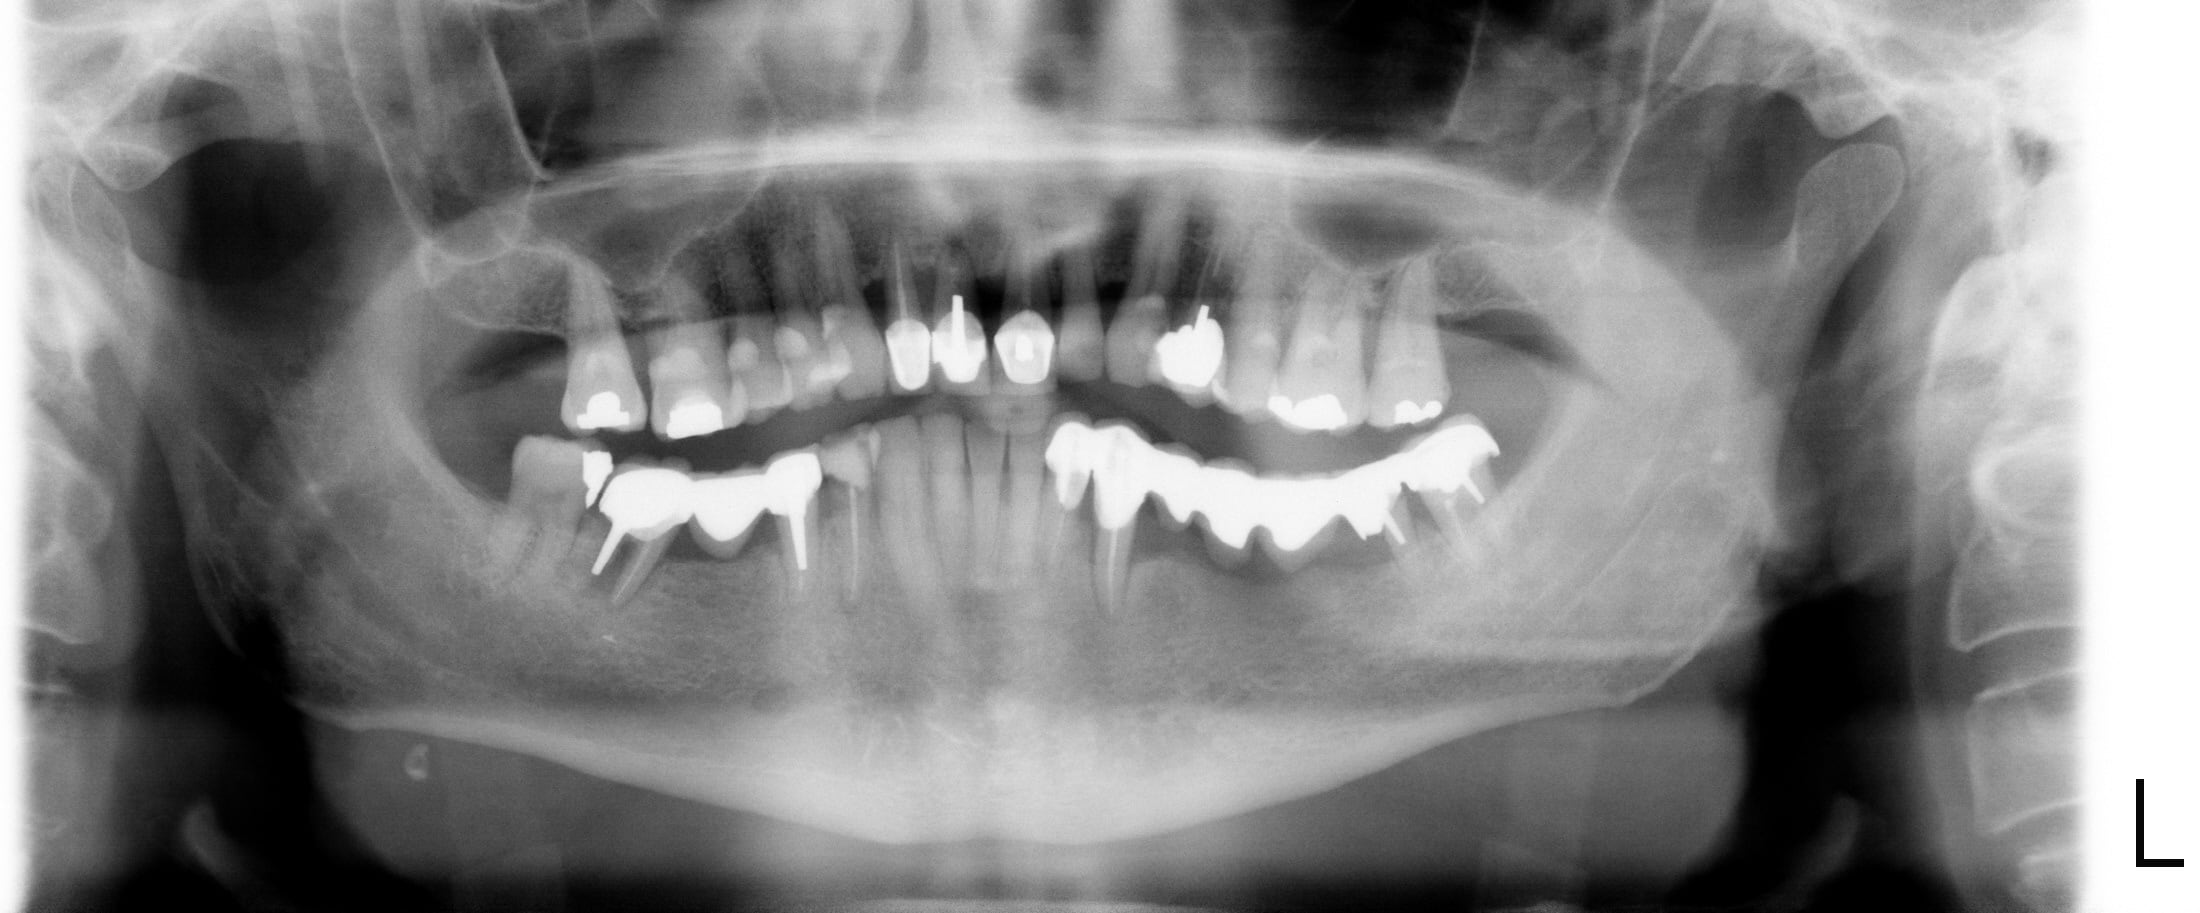

Cela a été posé il y a 26 ans, j'ai tout l'historique si tu as besoin avec les radios à l'origine.

je dois avoir beaucoup de cas comme cela au moins pour ceux qui ne sont pas morts, je peux chercher si cela n'est pas trop urgent.

Un bridge complet qui a plus de 30 ans 4 inters 12 22 et une petite reprise chirurgicale il y a deux ans je peux te faire un pano si tu veux après les fêtes.